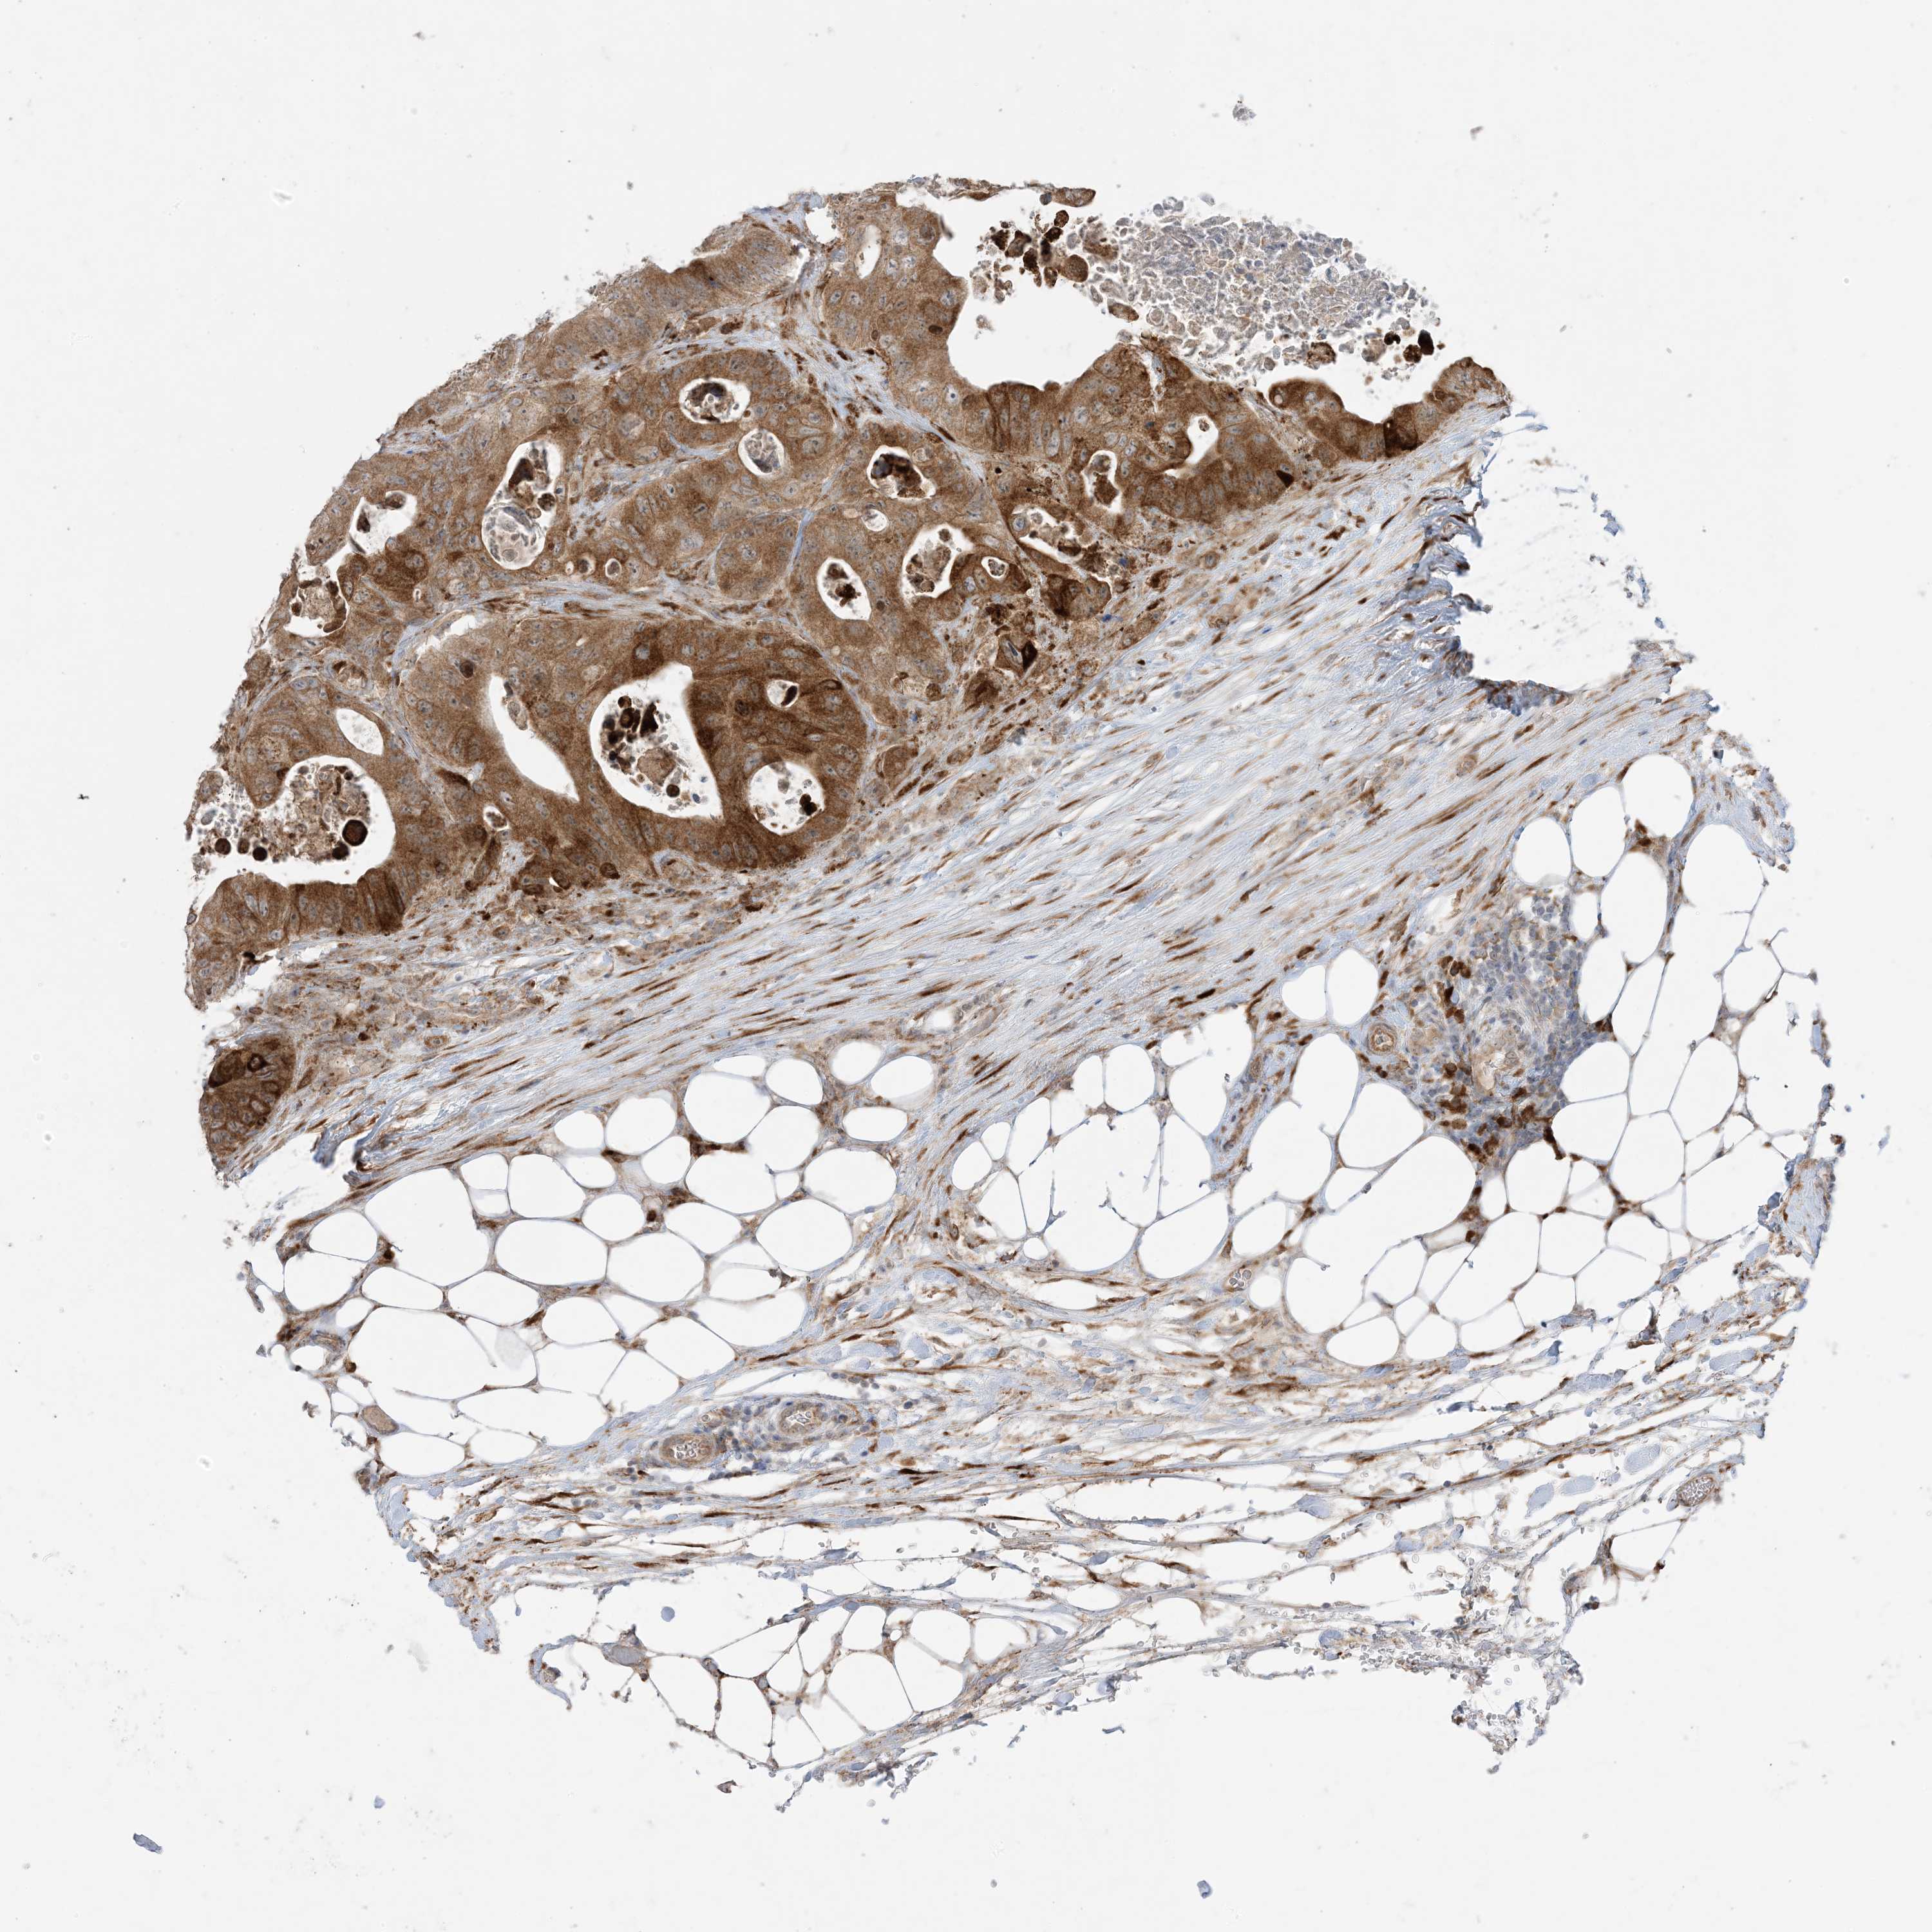

CANCER COLORECTAL CANCER Show tissue menu

Colorectal cancer

Human cancer

Colon adenocarcinoma